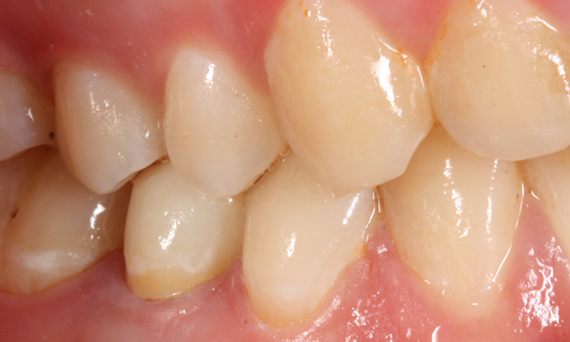

Before

Large insufficiency of the composite filling on tooth 16 with distal marginal ridge cracks, a lingual wall crack and distal recurrent decay.

After

Highly esthetic full-surface glass-ceramic crown.